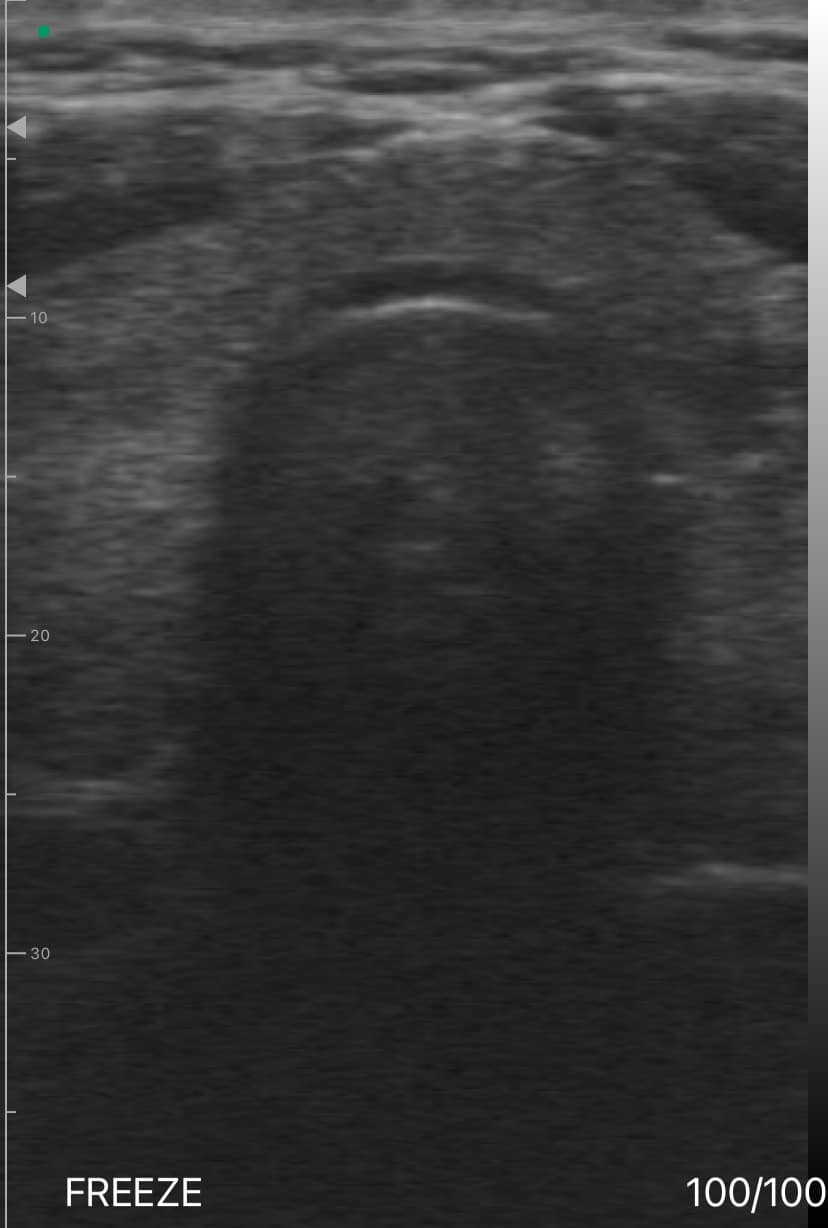

Dr. Emily Foster, an orthopedic surgeon at a Miami-based hospital, utilized the Dr. Sono Tri-Scan Max to dynamically assess subacromial impingement in a patient with shoulder pain. The patient presented with symptoms of rotator cuff tendinopathy and limited range of motion, which were suspected to be caused by impingement at the acromion.

Using the Dr. Sono Tri-Scan Max with a linear probe, Dr. Foster conducted a real-time dynamic ultrasound examination. The patient was instructed to move the shoulder through various positions while Dr. Foster carefully observed the subacromial space. The dynamic assessment revealed a reduction in the subacromial gap during specific movements, confirming the diagnosis of impingement.

Additionally, the ultrasound allowed Dr. Foster to evaluate the integrity of the rotator cuff tendons and surrounding structures and ensure that no significant tears or inflammation were present. The dynamic nature of the assessment provided crucial information about how the shoulder mechanics contributed to the impingement. Dr. Foster used this information to recommend targeted physical therapy for the patient, along with a cortisone injection to relieve inflammation. The real-time feedback provided by the Dr. Sono Tri-Scan Max was essential in creating an effective treatment strategy and offering the patient relief from their symptoms.